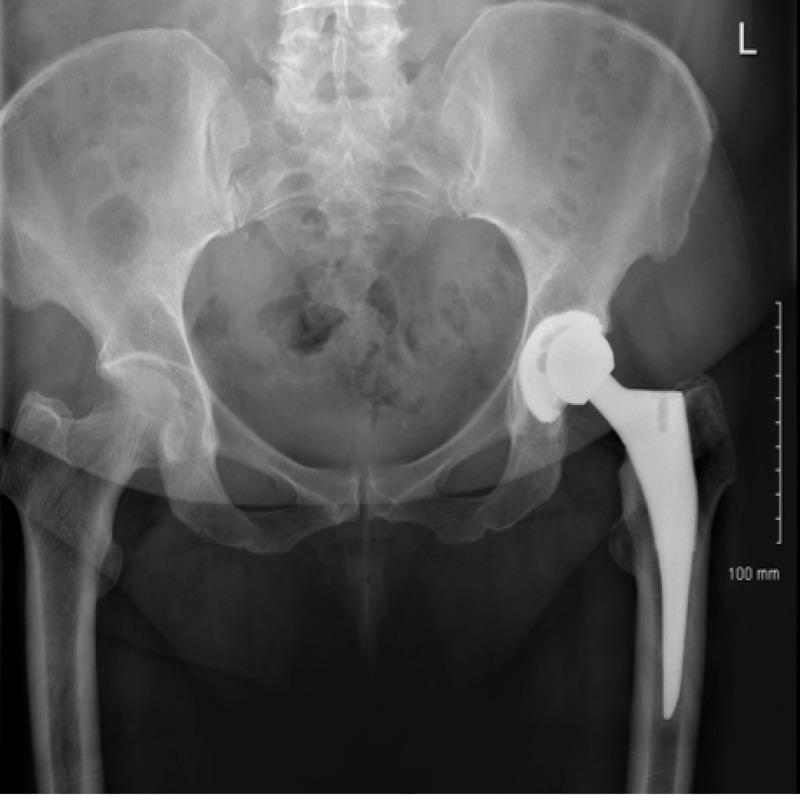

Acute Liner dissociation is a well-documented, but uncommon complication of total hip arthroplasty, yet the journey to diagnosis remains undefined. This clinical case report outlines the use of plain film arthrogram for diagnosis in a 53-year-old female who presented to the ED following a fall, describing symptoms of increasing groin pain, reduced range of movement, difficulty weight-bearing and a grinding sensation in her left hip, all on a background of total hip replacement two years ago. Examination revealed impaired flexion, rotation and abduction while AP pelvic X-ray confirmed mild eccentric placement of the femoral head, and lateral X-ray proved joint enlocation. An arthrogram of the left hip was performed the following day with injection of 4mls of iodinated contrast injected into the joint. Inferior dissociation of the liner from the shell was evident. The femoral head and liner were replaced two days later, and the liner was found to have shearing and gross plastic deformation at the rim. The patient reported immediate relief from the groin pain and was discharged on the fourth day postoperatively. This shows how plain film imaging fails in diagnosing acute liner dissociation dynamic fluoroscopic tests, post-arthrography CT and metal artifact reduction sequence magnetic resonance imaging (MARS MRI) have previously been proposed despite their associated wait-time, radiation exposure and financial costs. This case report highlights the role of plain film arthrography as a low risk and low-cost diagnostic tool. The report also suggests the incorporation of radio-dense markers in liners to facilitate the use of arthrography when diagnosing dissociation, also raising awareness of prevention and recognition in what may be an under-reported complication of hip arthroplasty.

急性髋臼衬垫分离是全髋关节置换术一种有充分文献记载但并不常见的并发症,然而其诊断过程仍不明确。本临床病例报告概述了在一名53岁女性患者中的应用,该患者在跌倒后前往急诊科就诊,自述腹股沟疼痛加剧、活动范围减小、负重困难以及左髋有摩擦感,所有这些症状均出现在两年前进行全髋关节置换术之后。检查发现屈曲、旋转和外展功能受损,前后位骨盆X线片证实股骨头轻度偏心放置,侧位X线片显示关节脱位。次日对左髋进行了关节造影,向关节内注入了4毫升碘化造影剂。髋臼衬垫与髋臼杯的下方分离明显。两天后更换了股骨头和髋臼衬垫,发现髋臼衬垫边缘有剪切和严重的塑性变形。患者报告腹股沟疼痛立即缓解,并在术后第四天出院。这表明普通X线成像在诊断急性髋臼衬垫分离方面存在不足,尽管之前有人提出动态荧光透视检查、关节造影后CT和金属伪影减少序列磁共振成像(MARS MRI),但它们存在相关的等待时间、辐射暴露和经济成本。本病例报告强调了普通X线关节造影作为一种低风险、低成本诊断工具的作用。该报告还建议在髋臼衬垫中加入放射性致密标记物,以便在诊断分离时便于使用关节造影,同时也提高了对髋关节置换术这一可能未被充分报道的并发症的预防和识别意识。